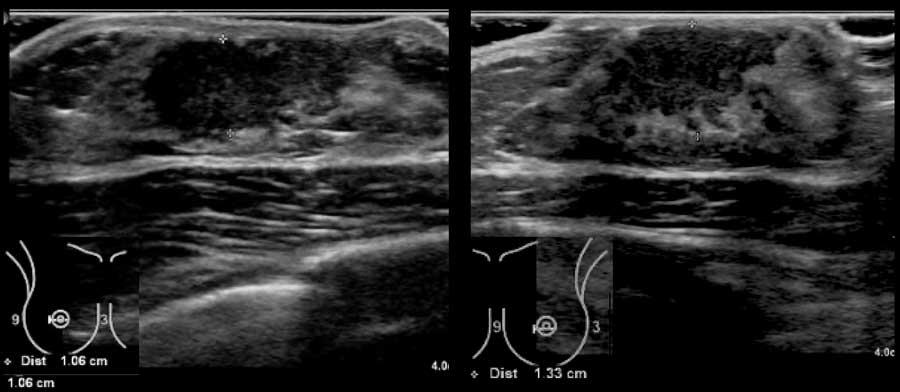

Các hình ảnh này thuộc về một phụ nữ 50 tuổi đến khám vì sờ thấy các khối ở vùng nách, tương ứng với các hạch bạch huyết to, hình tròn, giảm âm.

Tiếp theo đó, siêu âm tuyến vú được thực hiện và phát hiện một tổn thương ung thư nhỏ, giảm âm, bờ không đều, không sờ thấy được trên lâm sàng.